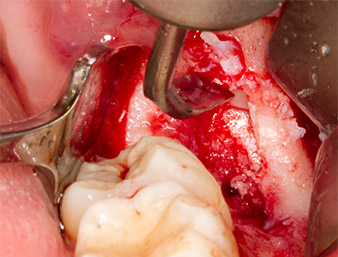

Dopo l'anestesia tronculare e l'anestesia locale, il sito operatorio è stato aperto e il tessuto molle esposto per l'accesso retromolare boccale (Fig. 3).

Il tessuto al di sopra del residuo di radice non era completamente ossificato ed era costituito per la maggior parte da tessuto di granulazione modificato dall'infiammazione (Fig. 4).